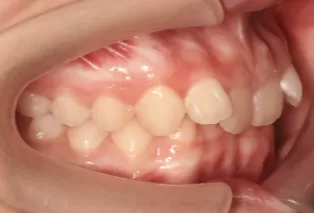

Intraoral photos